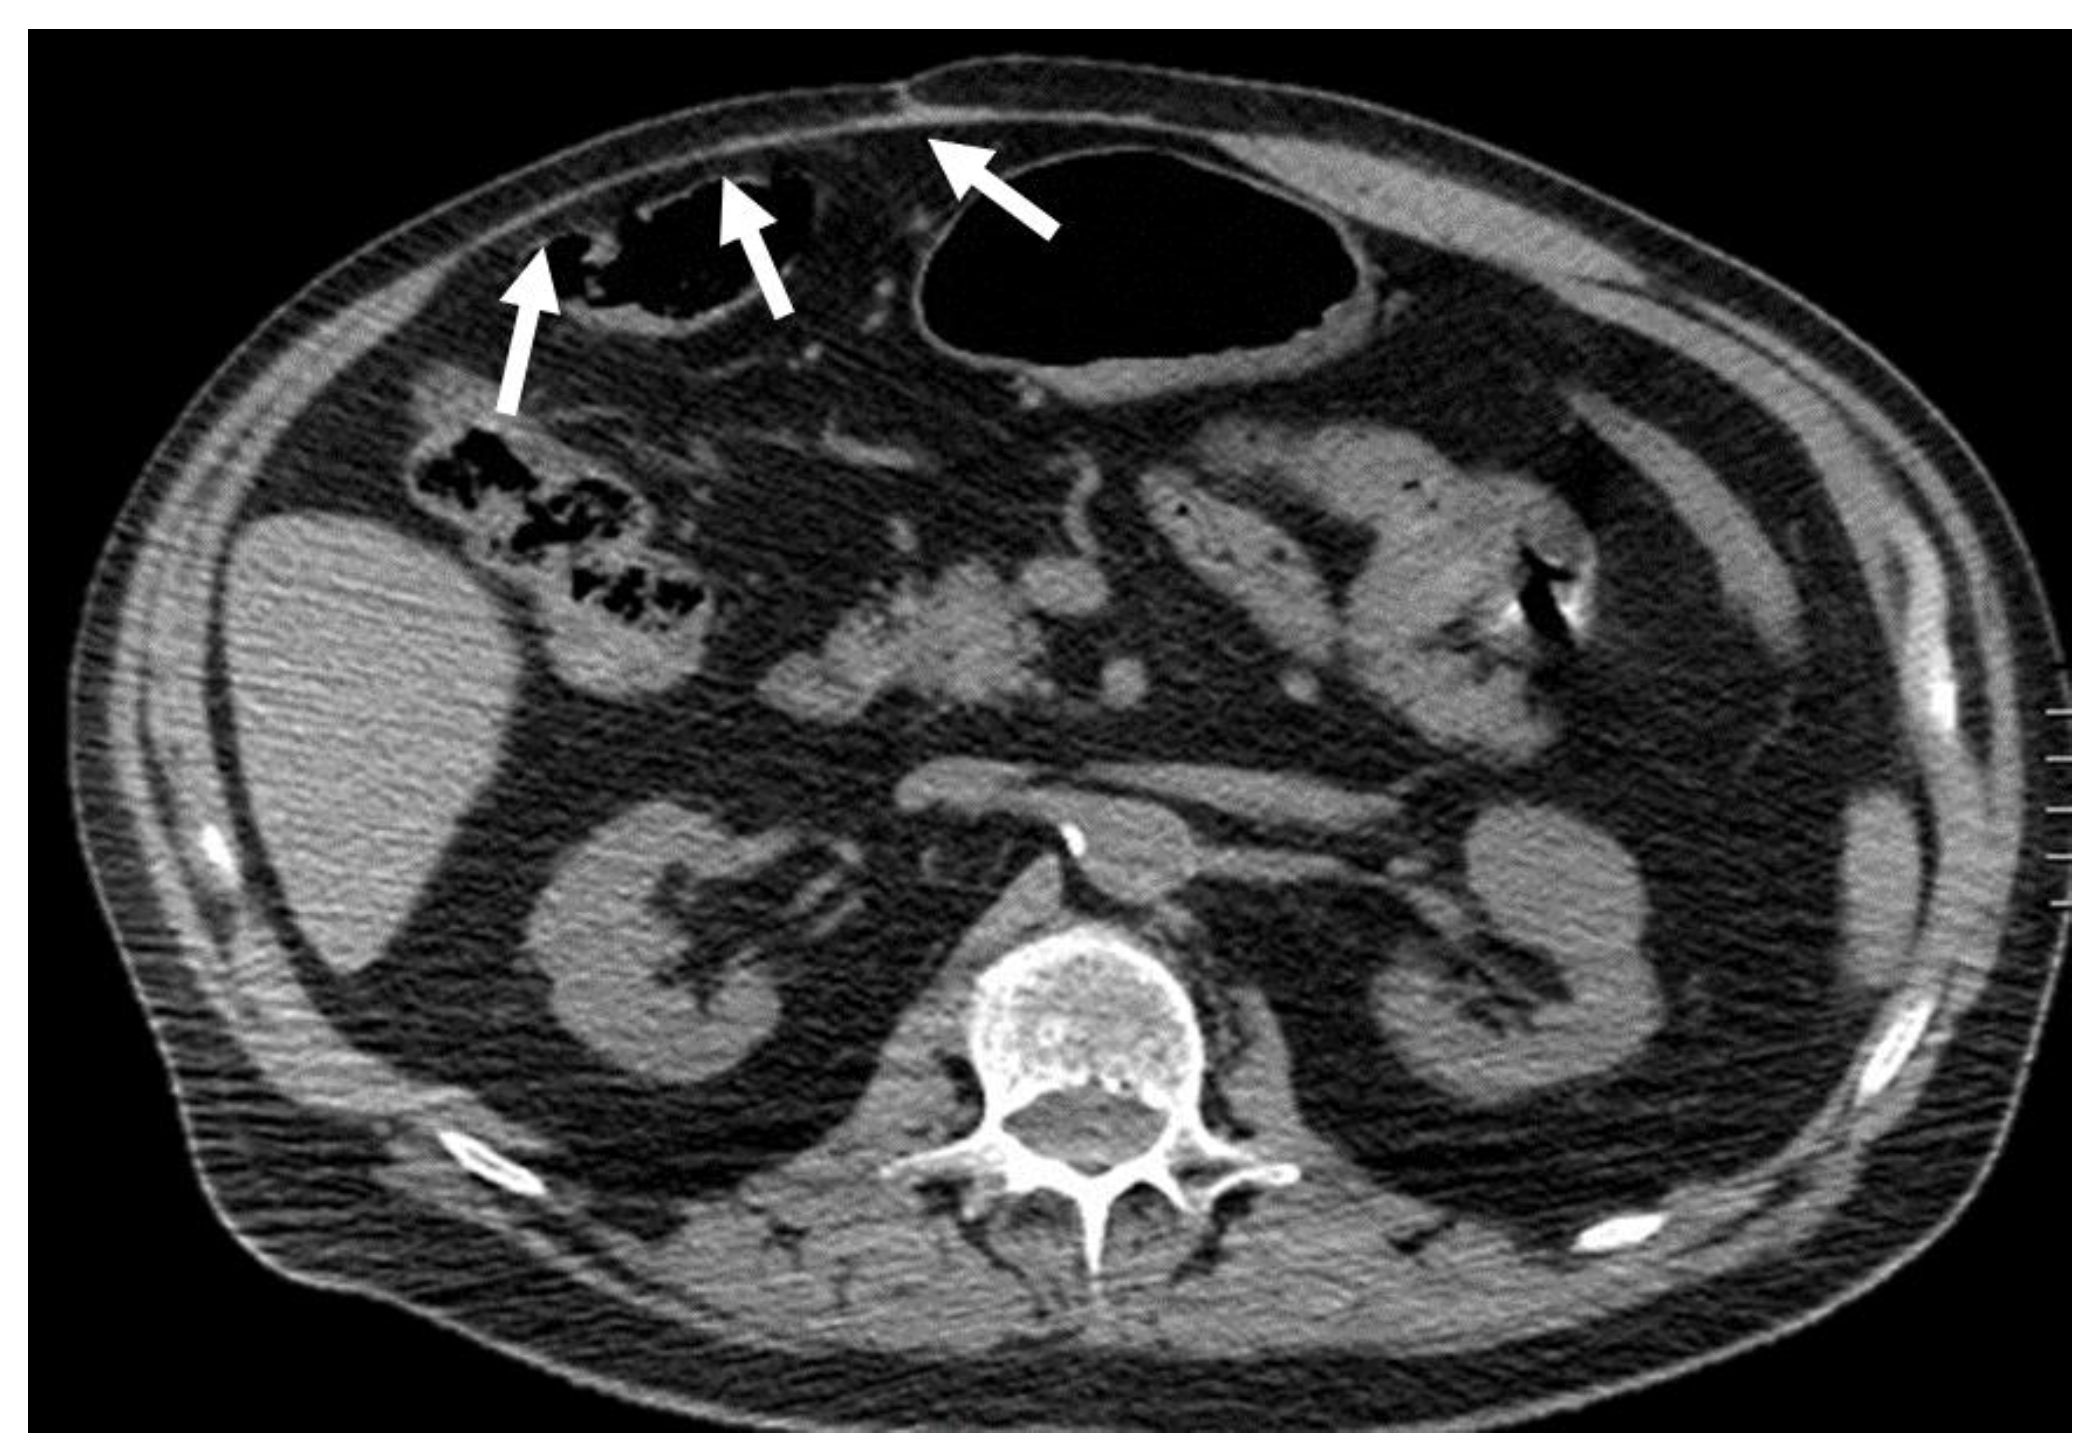

Figure 2. CT appearance of necrotizing fasciitis in a 58-year-old woman with a recent left lower limb open wound who arrived at the ER in septic shock. Arterial phase axial CT scan reveals the presence of free air in the fascial planes of the left lateral and posterior abdominal wall, with fascial thickening and lack of muscular enhancement, as compared to its counterpart (arrows). These elements are suggestive of necrotizing fasciitis. The patient was promptly referred to surgery, but she died on the operatory table.

On CT, the most suggestive findings of NF are the thickening of the fascia and a large amount of subcutaneous gas, although the latter is not specific [10,11,12] (Figure 2).

Focal or diffuse non-enhancing areas [10,11] with extensive multi-compartmental involvement (meaning that at least three muscle compartments are involved in this change) are another typical finding.